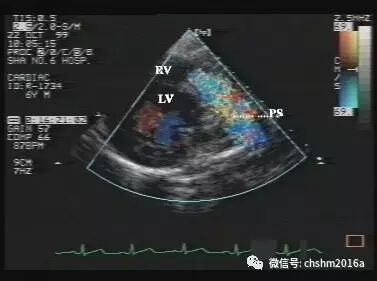

3.彩色多普勒超声心动图

显示红色为主、多色镶嵌的血流束穿越室间隔缺损处进入右心室。

彩超伪像是什么先天性心脏病超声诊断(超声梦影像医生集团 CCM)_https://www.jmylbn.com_新闻资讯_第9张

图2.3.7   室间隔缺损彩色分流束进入右室(局部放大图)

彩色多普勒超声心动图在诊断室缺中可确定室间隔缺损的部位、直径,判定室间隔缺损分流方向,分流量。